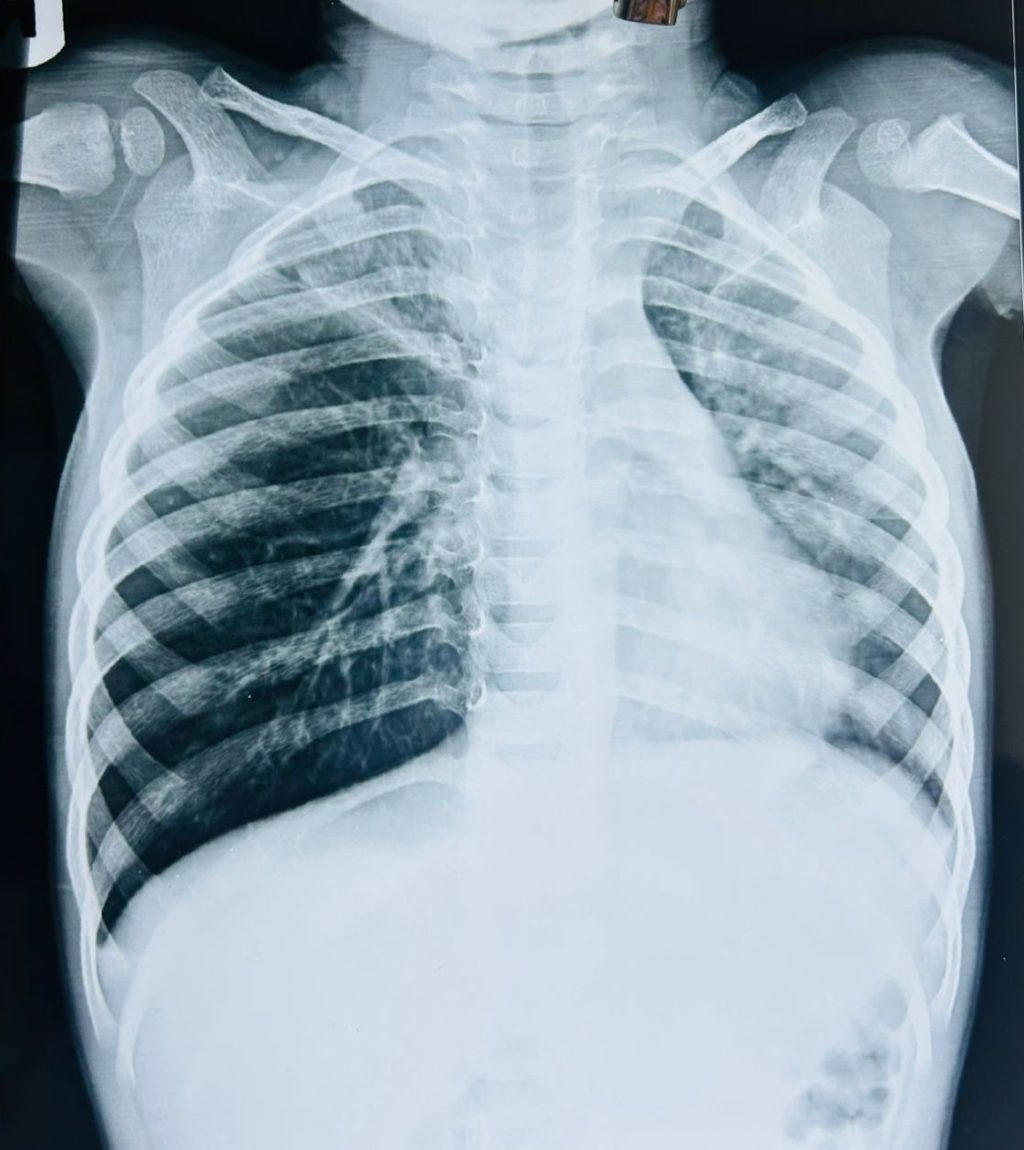

CT SCANNED SUGGESTIVE OF CLE, BRONCHOSCOPY FOUND FOREIGN BODY

(A 2-year-old boy, was admitted because of bad cough, cold ON AND OFF SINCE LAST 1 MONTH AND fever, and fast breathing OF RECENT ORIGIN . On checking, WE found that air was not going properly into his lungs, so he was given WAR oxygen, antibiotics, fluids, and nebulization. Blood tests showed infection. A chest X-ray showed lung infection and swelling of one lung. Since the problem started after eating groundnuts, doctors thought something might be stuck in his breathing pipe. A CT scan was done and showed narrowing of the airway AND  CHANGES OF CONGINITAL LOBAR EMPHYSEMA IN RIGHT SIDE WHICH NEED SURGICAL REMOVAL. So He was sent to a higher hospital FOR SAME, where SURGEON did a bronchoscopy FIRST and found a peanut stuck inside the airway. It was removed, and no surgery was needed. After removal, BABY improved quickly and recovered well.

Key lesson: (Always look at the child’s symptoms and condition, not only test reports.)